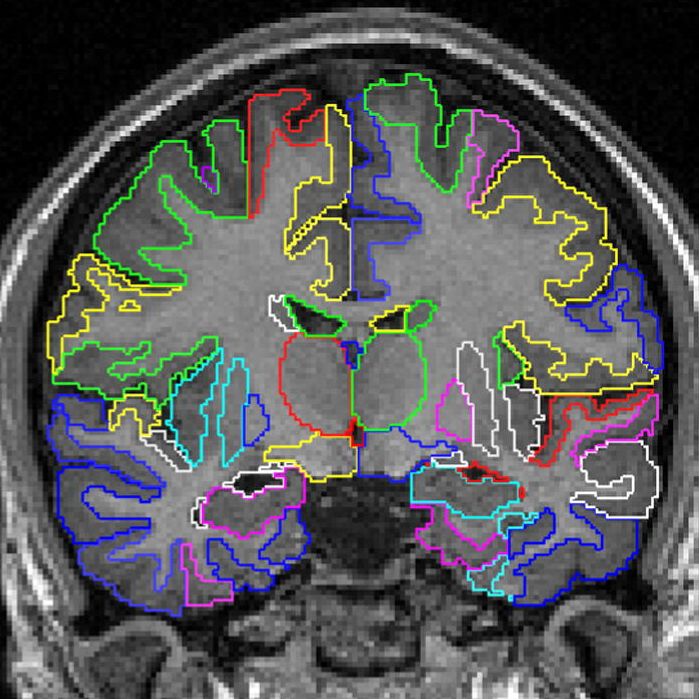

3、Data augmentation using learned transformations for one-shot medical image segmentation(利用学习变换进行数据增强,实现one-shot医学图像分割)

摘要图像分割是医学应用中的一个重要课题。基于卷积神经网络的方法获得了最先进的精度;然而,它们通常依赖于带有大型标记数据集的监督训练。医学图像的标注需要大量的专业知识和时间,而典型的手工调优的数据增强方法无法捕捉这些图像中的复杂变化。我们提出了一种自动数据增强方法来合成标记医学图像。我们在分割磁共振成像(MRI)脑扫描的任务中展示了我们的方法。我们的方法只需要一次分段扫描,并利用半监督方法中的其他未标记扫描。我们从图像中学习转换模型,并使用该模型和带标记的示例来合成其他带标记的示例。每个转换都由空间变形场和强度变化组成,从而能够综合复杂的效果,如解剖学和图像采集过程的变化。我们展示了使用这些新示例训练有监督的分割器,对于one-shot生物医学图像分割的最先进方法有着显着的改进。我们的代码可以在https://github.com/xamyzhao/brainstorm上找到。